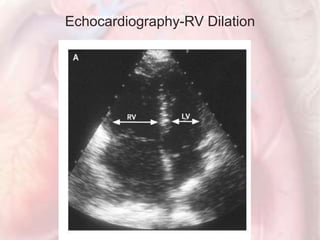

Echocardiography-RV Dilation

Echocardiograms before andafter Thrombolysis Echocardiography-RV Dilation